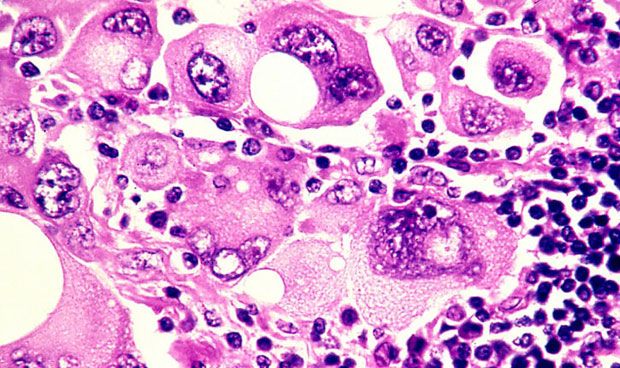

Científicos australianos han desarrollado el primer test para detectar en sangre el melanoma en estadios precoces. Los ensayos con 209 personas mostraron eficacia en el 81,5 por ciento de los casos.

La prueba detecta 10 combinaciones de anticuerpos que produce el cuerpo como respuesta al tumor

Esta prueba funciona detectando 10 combinaciones de anticuerpos producidos por el cuerpo en respuesta al melanoma. El próximo paso es aumentar la sensibilidad del test, llevar a cabo ensayos clínicos más amplios y probas sus resultados frente a biopsia.